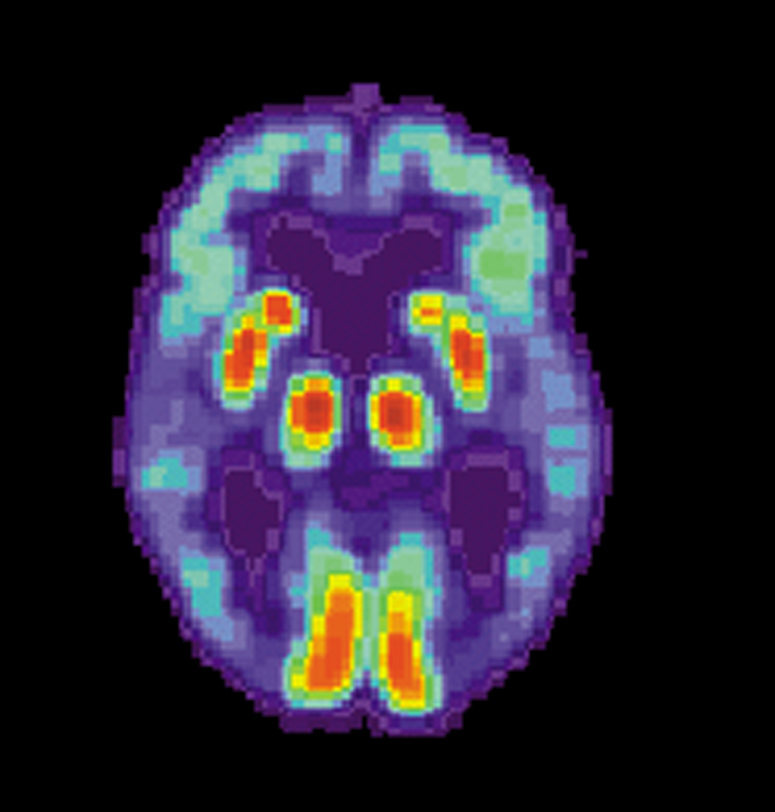

The Movement to Protect Your Mind From Brain-Computer Technologies

Recording memories, reading thoughts, and manipulating what another person sees through a device in their brain may seem like science fiction plots about a distant and troubled future. But a team of multi-disciplinary researchers say the first steps to inventing these technologies have already arrived. Through a concept called “neuro rights,” they want to put in place safeguards for our most precious biological possessions: our mind.

Meet the Brain Banker Who Keeps Thousands of Brains In His Lab In the Bronx

Dr. Vahram Haroutunian opened the plastic tupperware with a careful, rigid pop. Inside are over a dozen pink, carefully freeze-packed slices of a human......